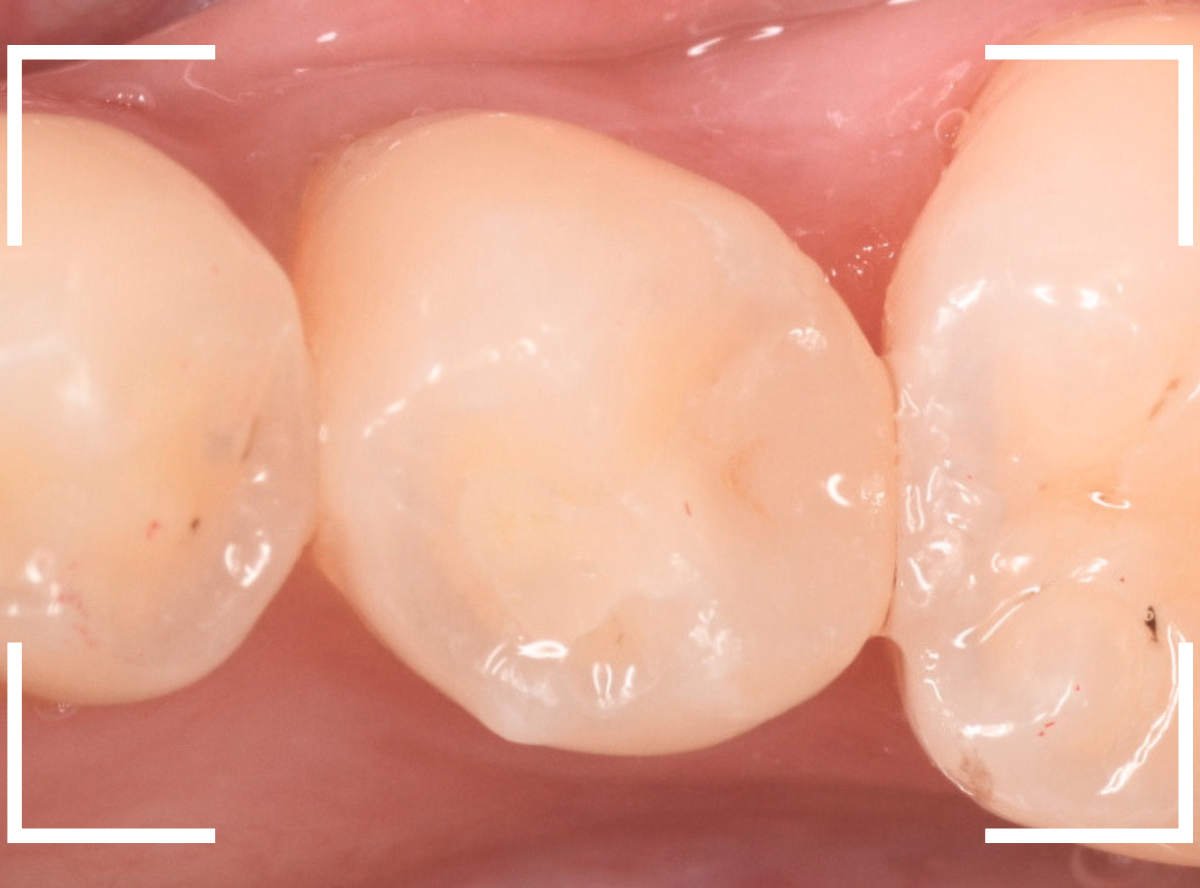

治療後の状態です。

自然な仕上がりで、患者さんにもご満足いただけました。